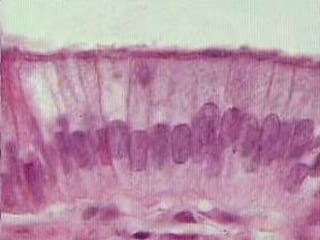

La superficie de la mucosa consiste en un epitelio simple cilíndrico.

Estas células epiteliales altas poseen 4 características:

1. Abundantes microvellosidades apicales cortas y poco desarrolladas.

2. Complejos de unión apicales que unen células contiguas.

3. Concentraciones de mitocondrias ubicadas en el citoplasma basal y apical.

4. Pliegues laterales complejos.